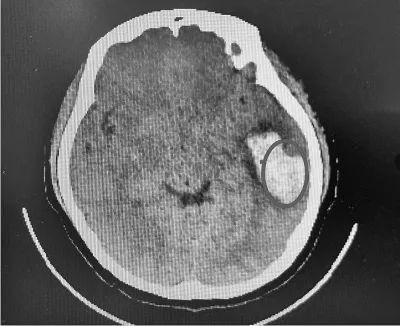

而在不久前的6月18日,河南郑州一位女大学生在KTV唱了一曲《凉凉》,随后出现恶心、呕吐、头晕头痛等,经检查后发现为脑出血,而且出血量比较大,有将近30毫升。

右侧圆圈处为出血位置